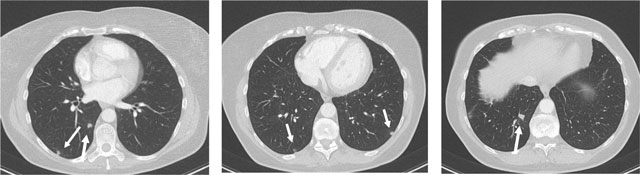

Figure 2

CT thorax: multiple small nodular lung lesions (arrows).